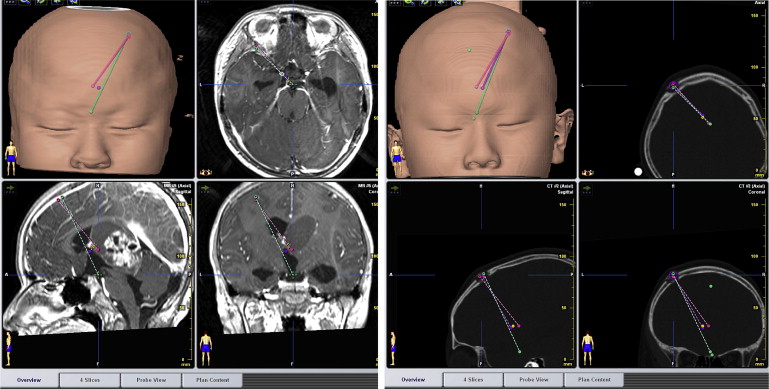

ETV and ETB trajectory reconstruction: The preoperative MRI image and ...

Figure 2.

ETV and ETB trajectory reconstruction: The preoperative MRI image and postoperative CT images were fused together. The trajectories were drawn from the burr hole to the sites of the ETV and ETB in the three-dimensional reconstruction images. CT = computed tomography; ETB = endoscopic tumor biopsy; ETV = endoscopic third ventriculostomy; MRI = magnetic resonance imaging.